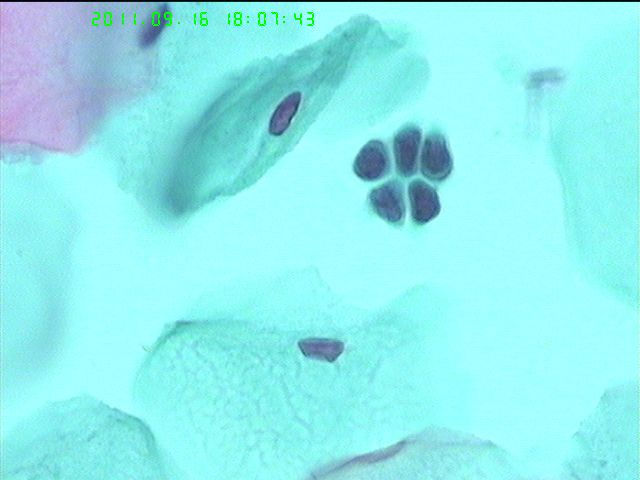

子宫原位癌术后LCT

如题

复发了

有子宫内膜细胞,应该是做冷刀。

AGC